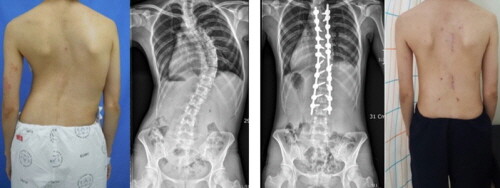

연구 결과, 척추측만증 만곡의 교정은 수술 전 평균 59.8도에서 수술 후 18.6도로 약 68.9%의 우수한 교정률을 보였으며 출혈량은 평균 846 mL, 입원 기간은 평균 8.5일로 줄어들어 변형 교정의 우수성과 함께 높은 안정성을 보였다.

| ▲청소년기 특발성 척추측만증 환자에서 최소침습수술 후 만곡이 교정된 사진 (사진=상계백병원 제공) |